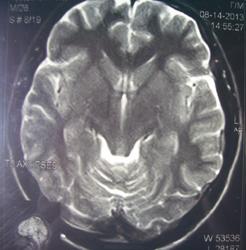

При изучении МРТ снимков головного мозга невролог указала на наличие маленьких очажков на коре головного мозга, порекомендовав обратиться за лечением к нейрохирургам. Голова также продолжает болеть, еще стали кисти рук неметь и прочие симптомы. Можете ли вы указать, имеются ли эти маленькие очажки на коре головного мозга и где именно?

Алексей, очагов достоверно не вижу, а вот на верхнечелюстную пазуху нужно обратить внимание-есть ее воспалительные изменения в виде утолщения слизистой.

а какие либо гематомы видите? просто лечащий врач невролог, указал наличие маленьких очагов воспаления на коре головного мозга!!! Посмотрите пожалуйста повнимательнее снимок 2/6?имеется ли не заращение заднего апофиза тела С5?

а какие либо гематомы видите? просто лечащий врач невролог, указал наличие маленьких очагов воспаления на коре головного мозга!!! Посмотрите пожалуйста повнимательнее снимок 2/6? имеется ли не заращение заднего апофиза тела С5?